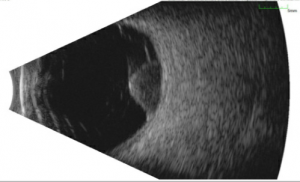

Ultrasound

This is the primary diagnostic test that confirms the diagnosis of melanoma. Ultrasound also is useful in determining the size, e.g. thickness (apical height) and basal dimension, extraocular extension (such as scleral nodules), and document growth during the follow up of a suspicious nevus/small melanoma.

- Standardized A-mode: Posterior uveal melanomas classically show medium to low internal reflectivity (88%), often in a decrescendo fashion, a.k.a, positive angle kappa, with regularity of structure. The internal blood flow (vascularity) of the tumor can be seen as a fast movement of the internal spikes. Uncommonly, a large melanoma may be more irregular, particularly if there is necrosis.

- B-mode: Shapes: Dome-shaped is most common, mushroom-shaped, i.e. collar button is the most classic shape, and an irregular shape is uncommon. Other features: acoustically hollow zone within the tumor, choroidal excavation, and subretinal fluid.